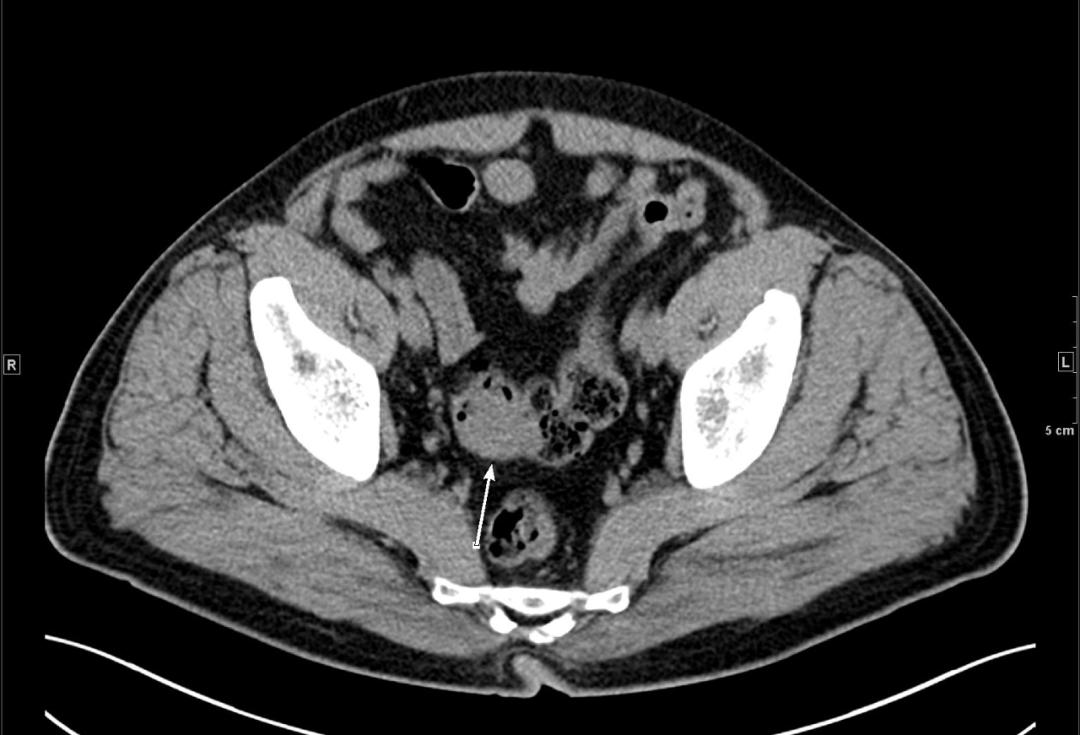

结核性胸膜炎; 腹部ct示:双侧髂腰肌脓肿形成,腹腔积液,肠结核,结核